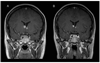

The authors present a 21-year-old woman who has been receiving rapamycin for 5 months for bilateral subependymal giant cell astrocytomas. The patient was started at a dose of 0.2 mg/kg/day. Levels were maintained between 11 and 13 ng/mL. Magnetic resonance imaging of the brain 2(1/2) months after initiating rapamycin demonstrated a decrease in size of both astrocytomas (11 to 7.5 mm on the right and 8 to 5 mm on the left). Further studies are needed with prolonged observation to confirm these findings, determine the length of necessary treatment, and evaluate recurrence risk after discontinuation of rapamycin.